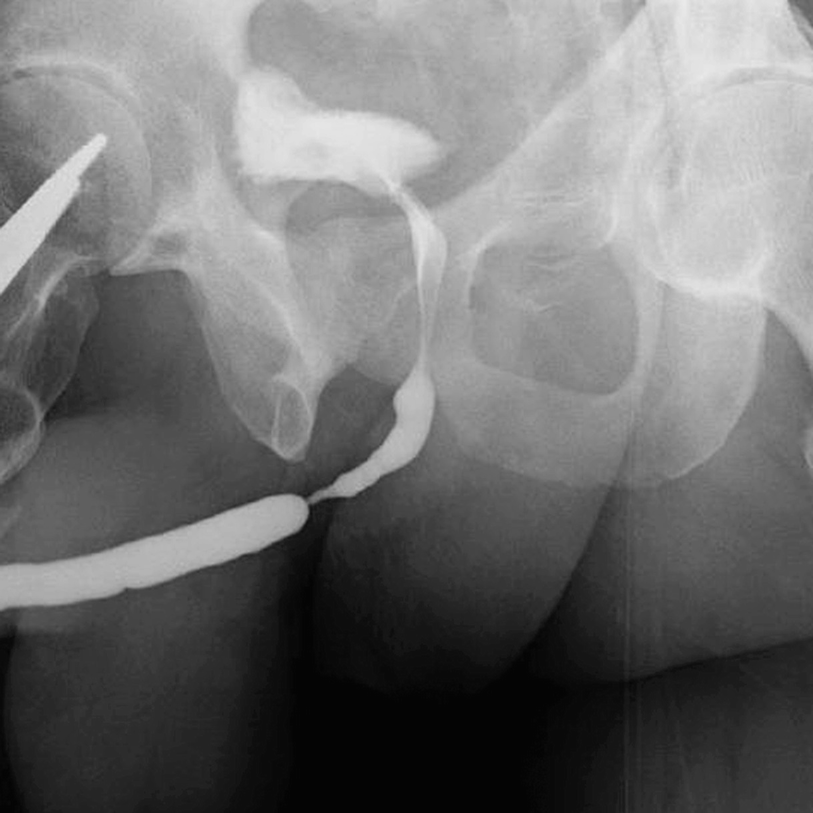

Retrograde urethrogram demonstrating a focally high-grade 2 cm mid bulbar urethral stricture